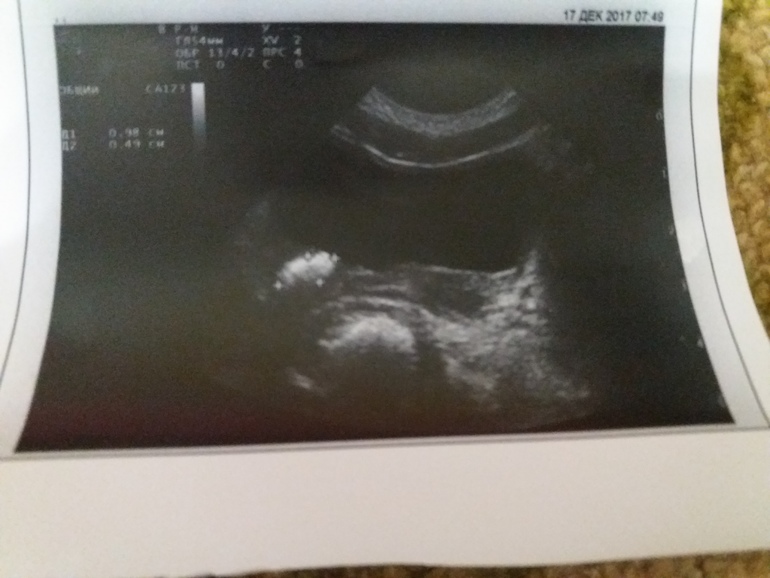

Ребенок родился 29 недель, 1050гр, 40 дней ивл. Сепсис, полиорганная недостаточность, предположительно в это время образовался камень в левой почке. Обнаружили камень в 5 мес. Размер около 0.7 см. По литос камнеобразования не было, было решено за ним наблюдать.

Сейчас ребенку 3 года. Рост около 90см, вес 11500гр. Неделю назад обнаружили, что камень вышел из почки и находится в мочевом пузыре в устье мочеточника. Ребенка беспокоят частые и болезненные мочеиспускания, в моче эритроциты, лейкоциты, бактерии.